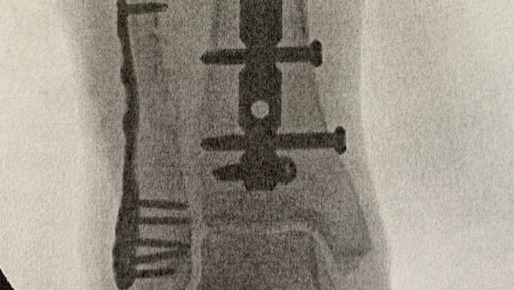

As some of you may have heard, my amazing wife Jennifer broke both the bones in her right leg on March 3rd. Luckily, it wasn't a compound fracture but pretty close to being so. She had an amazing team of surgeons put her back together and now she is on the long road to a healthy recovery. Racquetball is on hold and she is never roller skating again. As we deal with the mountain of medical costs we have dug into our reserves during her work hiatus. Jen is a free-lance, self-employed contractor working on various TV productions in the DFW Metroplex. Since the accident, Jen had to cancel several jobs that she was booked for. Like a lot of us, we are a dual income household so this income loss hurts a bit.